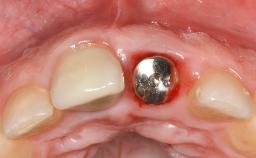

Due to their promising clinical performance, zirconia implants have recently become popular alternatives to titanium implants, particularly for areas with high esthetic demands (Holländer and coworkers 2016; Roehling and coworkers 2016; Lorenz and coworkers 2019). However, regardless of the reported high survival and success rates, zirconia implants were affected by peri-implant diseases over the short observation period, suggesting the importance of treating peri-implant diseases at zirconia implants (Becker and coworkers 2017). In their case, Frank Schwarz and Ausra Ramanauskaite present 3-year results following mechanical debridement alongside Er:YAG laser monotherapy.